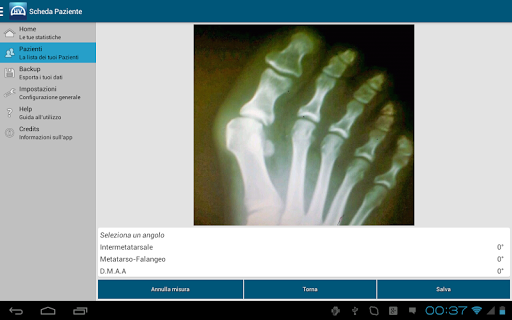

Inoltre, con Hallux Valgus potrete avere sempre con voi, non solo uno strumento di misura, ma anche un comodo archivio, consultabile in qualsiasi momento, in quanto tali misurazioni vengono automaticamente inserite nella “cartella clinica” del paziente in questione.

Hallux Valgus è lo strumento di misura ed archivio con il quale poter effettuare le misure in qualunque posto stiate effettuando la visita al paziente, trascrivendo, registrando, ed aggiornando per voi, tutti i dati nella “cartella clinica” di ogni paziente ed in maniera completamente automatica.